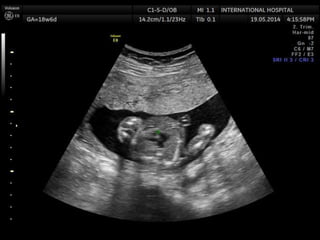

Patau Syndrome(Trisomy 13)

1st trimester

Increased NT

2nd trimester

Multiple major anomalies (>90%)

Holoprosencephaly

Midline facial anomalies

Cardiac defects

Polydactyly

Early IUGR